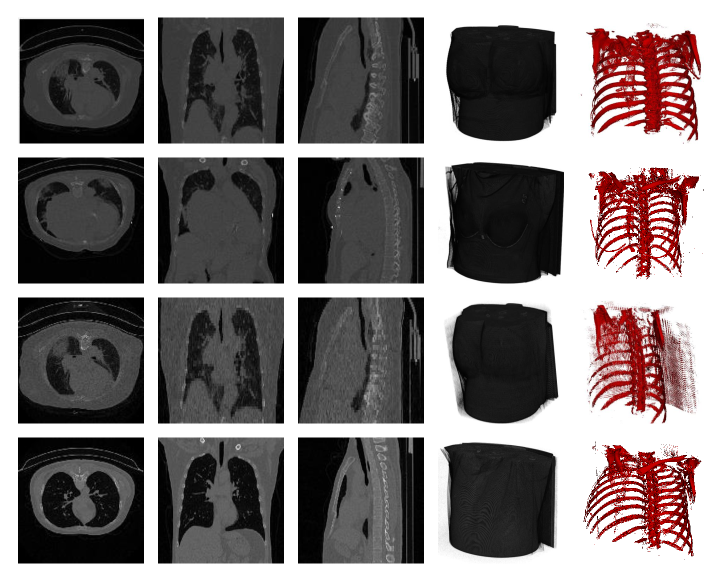

Refer to caption

Figure 6: Some random samples of CT scan 2D slices taken from CC-19 dataset.

Figure 7: This figure shows some selected samples from the “CC-19 dataset”. Each row represents different patient samples with various Hounsfield Unit (HU) for CT scans. The first there columns represent the XY, XZ, and YX plane of the 3D- volume respectively. The fourth column represents a whole 3D-Volume followed by a bone structure in the fifth column.